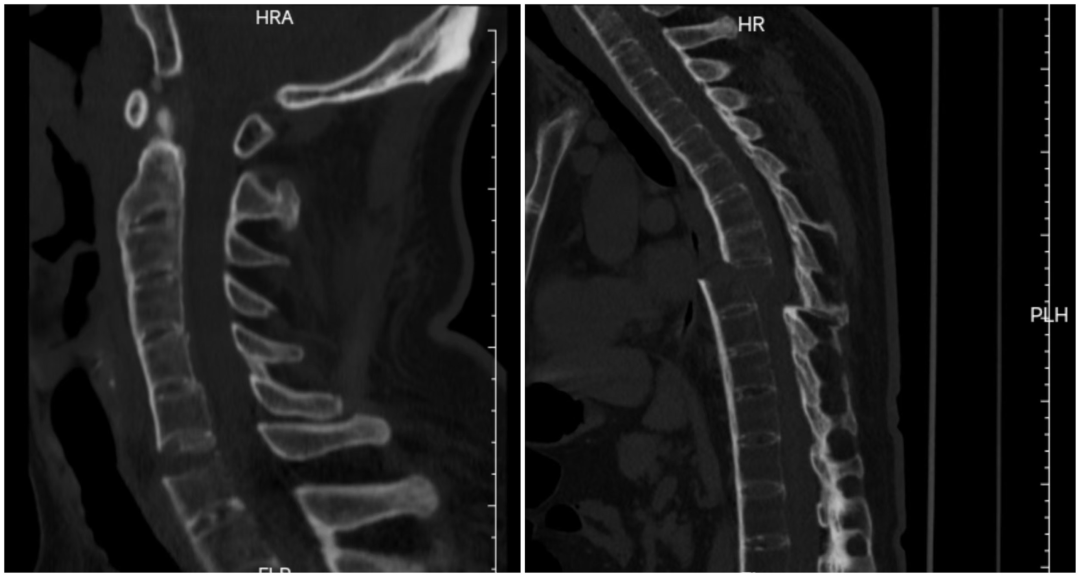

該患者因車禍導致頸椎橫貫性損傷,頸椎前方極度不穩定,同時合并胸椎完全性骨折脫位,椎體漂浮、脊柱連續性中斷。患者還有著多年的強直性脊柱炎病史,脊柱強直、骨質脆性高、穩定性極差,所幸入院時暫無明顯神經壓迫癥狀,四肢活動基本正常。然而,頸胸段脊柱序列已嚴重紊亂,麻醉后肌肉松弛,翻身等體位變化時稍有不慎,便可能引發脊髓嚴重受壓,導致癱瘓甚至呼吸循環衰竭,手術難度與風險堪稱脊柱外科手術的“珠穆朗瑪峰”。

該患者因車禍導致頸椎橫貫性損傷;同時合并胸椎完全性骨折脫位,椎體漂浮、脊柱連續性中斷。

手術當日,多學科團隊嚴陣以待,分階段有序推進。先行仰臥位頸椎閉合復位,再通過頸前5厘米微創切口完成頸椎前路內固定,顯著改善頸椎前方極度不穩定狀況,重建頸椎前柱穩定性。隨后,在神經電生理全程監測下,多學科協同完成Jackson床180°平穩翻轉,成功破解術中核心高危難點。最后,經后正中入路開展頸椎后路固定,并對胸椎骨折完全脫位部位進行減壓、精準復位與牢固內固定,徹底重建頸椎及胸椎脊柱正常序列。

經過13個小時的手術,患者的頸椎及胸椎脊柱序列得以重建

術后,患者經個性化康復治療,脊柱序列恢復正常,無癱瘓及神經功能障礙加重。目前,患者正有序開展康復訓練,即將重返正常生活。